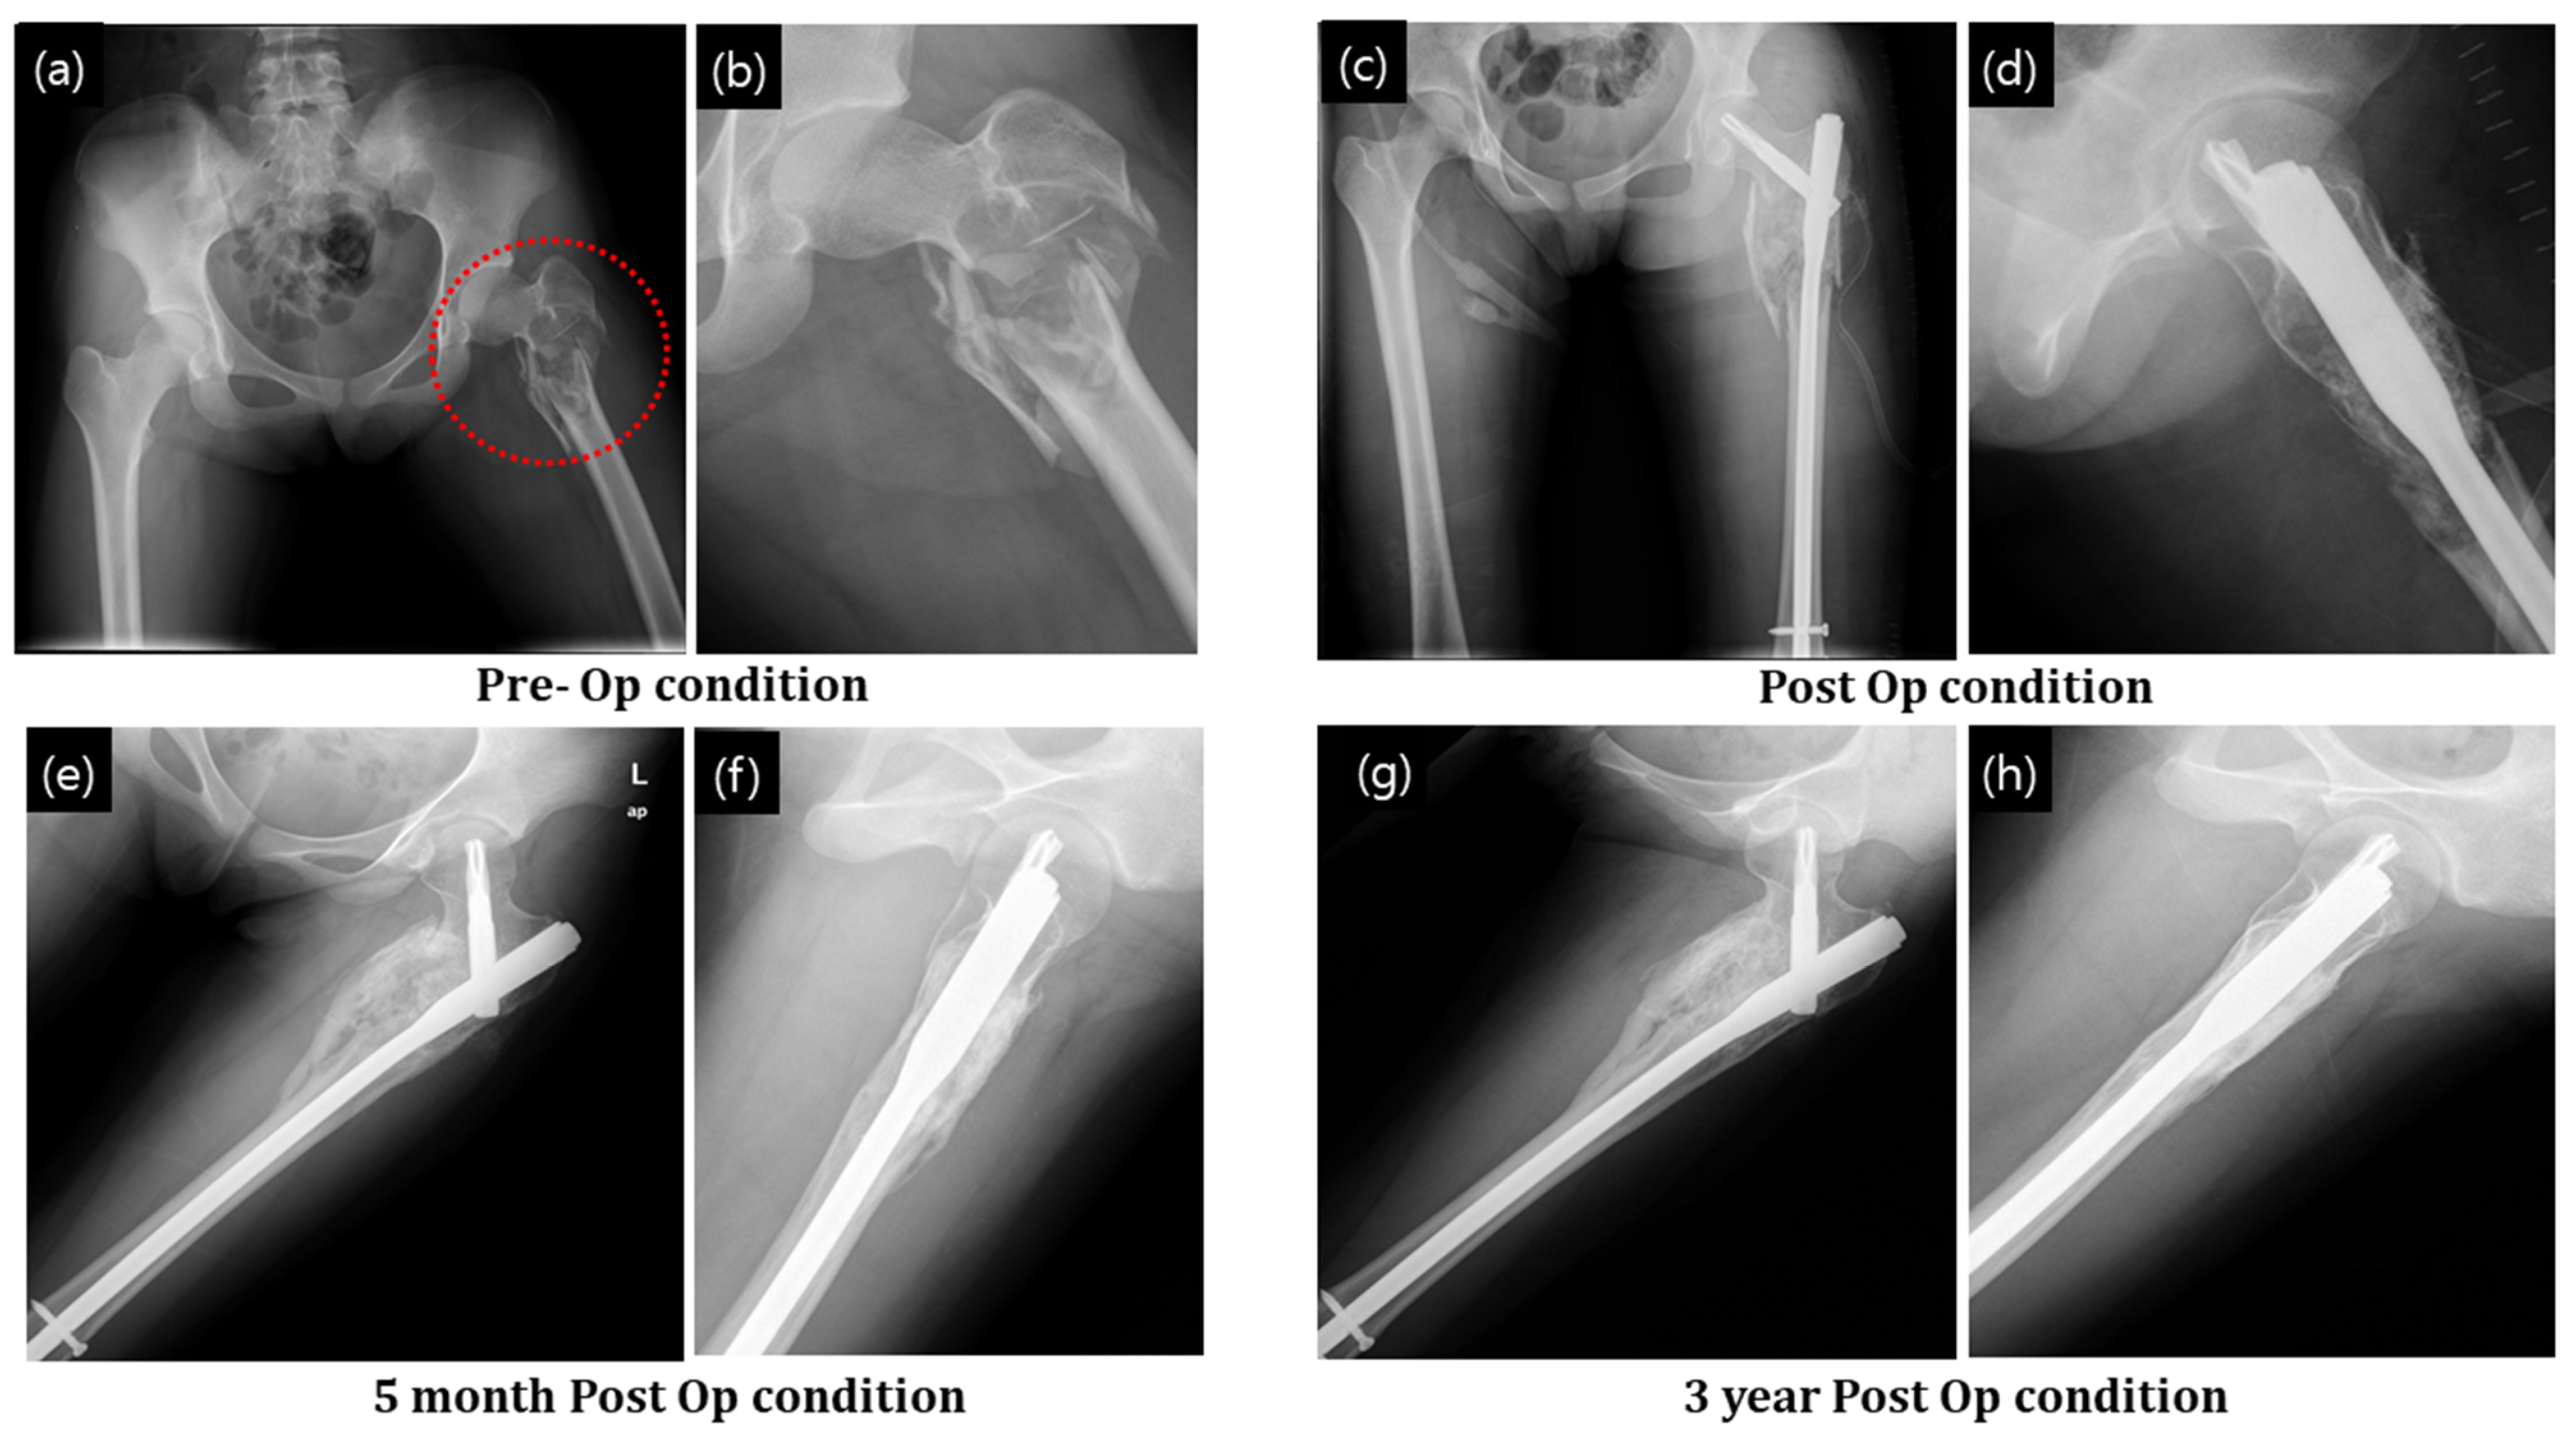

Figure 6a,b show the MRI of the fractured bone in both the coronal and axial planes. A compound fracture is evident in the MRI. The cyst formation complicated the resulting fracture (Figure 7a,b). Postoperative radiographs after stabilizing the femur by PFNA system and filling the bone defect with granular bone substitutes are shown in Figure 7c,d. At 5 months postoperatively, a significant progression in bone regeneration was observed along with a homogeneous and continuous bony structure. A substantial change in bone shape in association with additional growth down the fracture region, with stabilization of the contour fattening around the fracture zone, was observed (Figure 7g,h).

Figure 7. Fracture of intertrochanter region of the femur after a cyst formation was treated with granular bone substitute. (a,b) X-ray of the bone fracture, (c,d) postop condition with application of granular bone substitute and support implant, (e,f) after 5 months of operation and (g,h) after 3 years of operation. Red circle indicate defect zone with fracture.